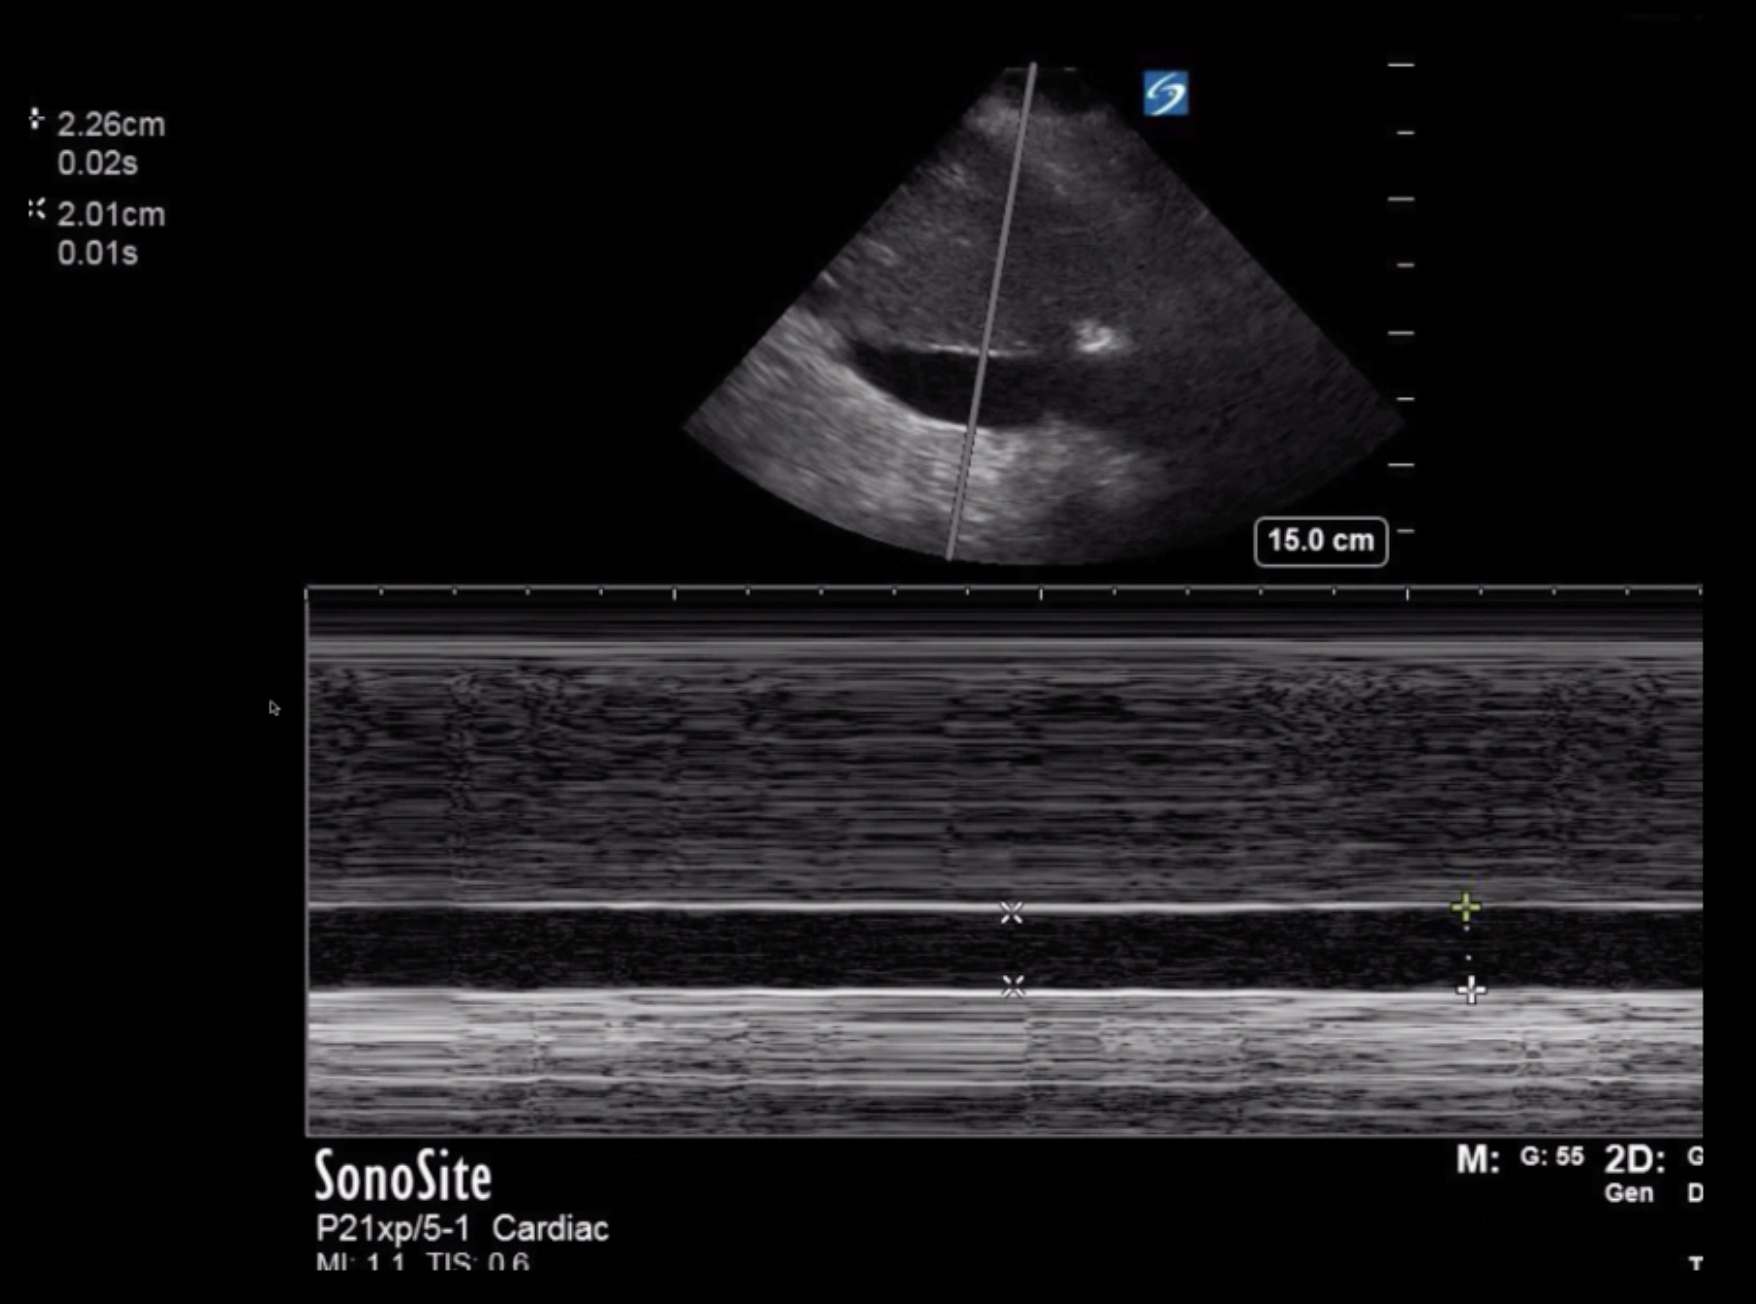

Cardiac 2 Central Venous Pressure (CVP) from Inferior Vena Cava (IVC) Measurement Image